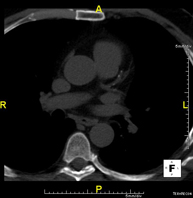

- TC Tórax

Prueba diagnóstica que consiste en obtener imágenes del tórax de alta definición anatómica (pulmones, corazón, mediastino, grandes vasos, caja torácica, etc.) mediante el empleo de un equipo de TC (Tomografía Computarizada). Dichas imágenes se estudian posteriormente en una estación de trabajo que permite reconstrucciones bidimendionales en diferentes planos del espacio y también reconstrucciones 3D (volumétricas). Algunos estudios requieren el empleo de contraste yodado para mejorar la definición de las imágenes. - Angio-TC Aorta torácica

Prueba diagnóstica que consiste en el estudio de la aorta torácica (principal arteria del tórax) mediante el empleo de un equipo de TC (Tomografía Computarizada). Esta técnica requiere el empleo de contraste yodado, y proporciona imágenes de alta definición anatómica. El uso del TCMD (TC Multidetector) acorta el tiempo de exploración, disminuye la dosis de radiación y mejora la calidad de la imagen. Gracias a los múltiples detectores, en determinados estudios se puede acoplar la obtención de la imagen con el latido cardíaco, técnica que permite el estudio de la válvula aórtica y de la raíz de la arteria aorta (primeros centímetros), donde el latido del corazón suele provocar múltiples artefactos de movimiento. - Angio-TC Arterias pulmonares (Estudio TEP, Tromboembolismo Pulmonar)